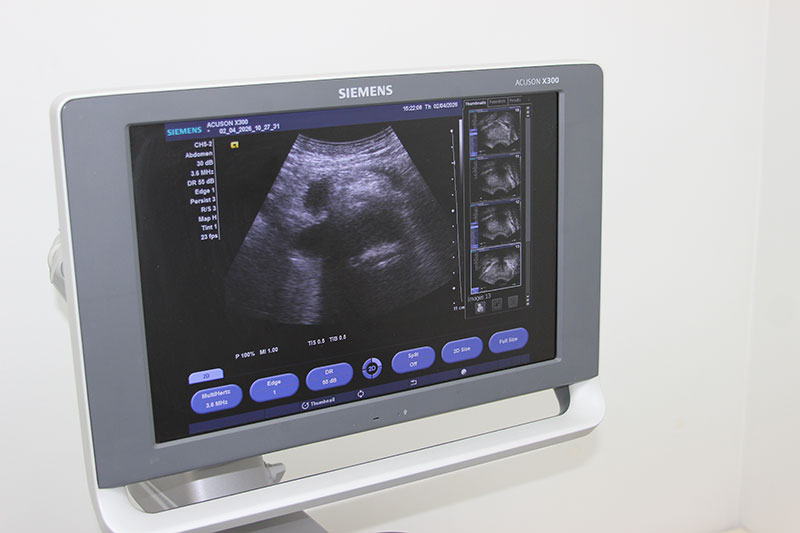

В ходе ультразвуковой диагностики печени доктор анализирует:

- Выявление объемных образований

Специалист оценивает наличие аномальных структур, таких как полости с жидкостью (кисты), доброкачественные опухоли (гемангиомы) или злокачественные новообразования.

Процедура фиксирует диффузные патологии (в самом органе) или локальные очаги воспалений. Для уточнения полученной информации используют компьютерный допплер.